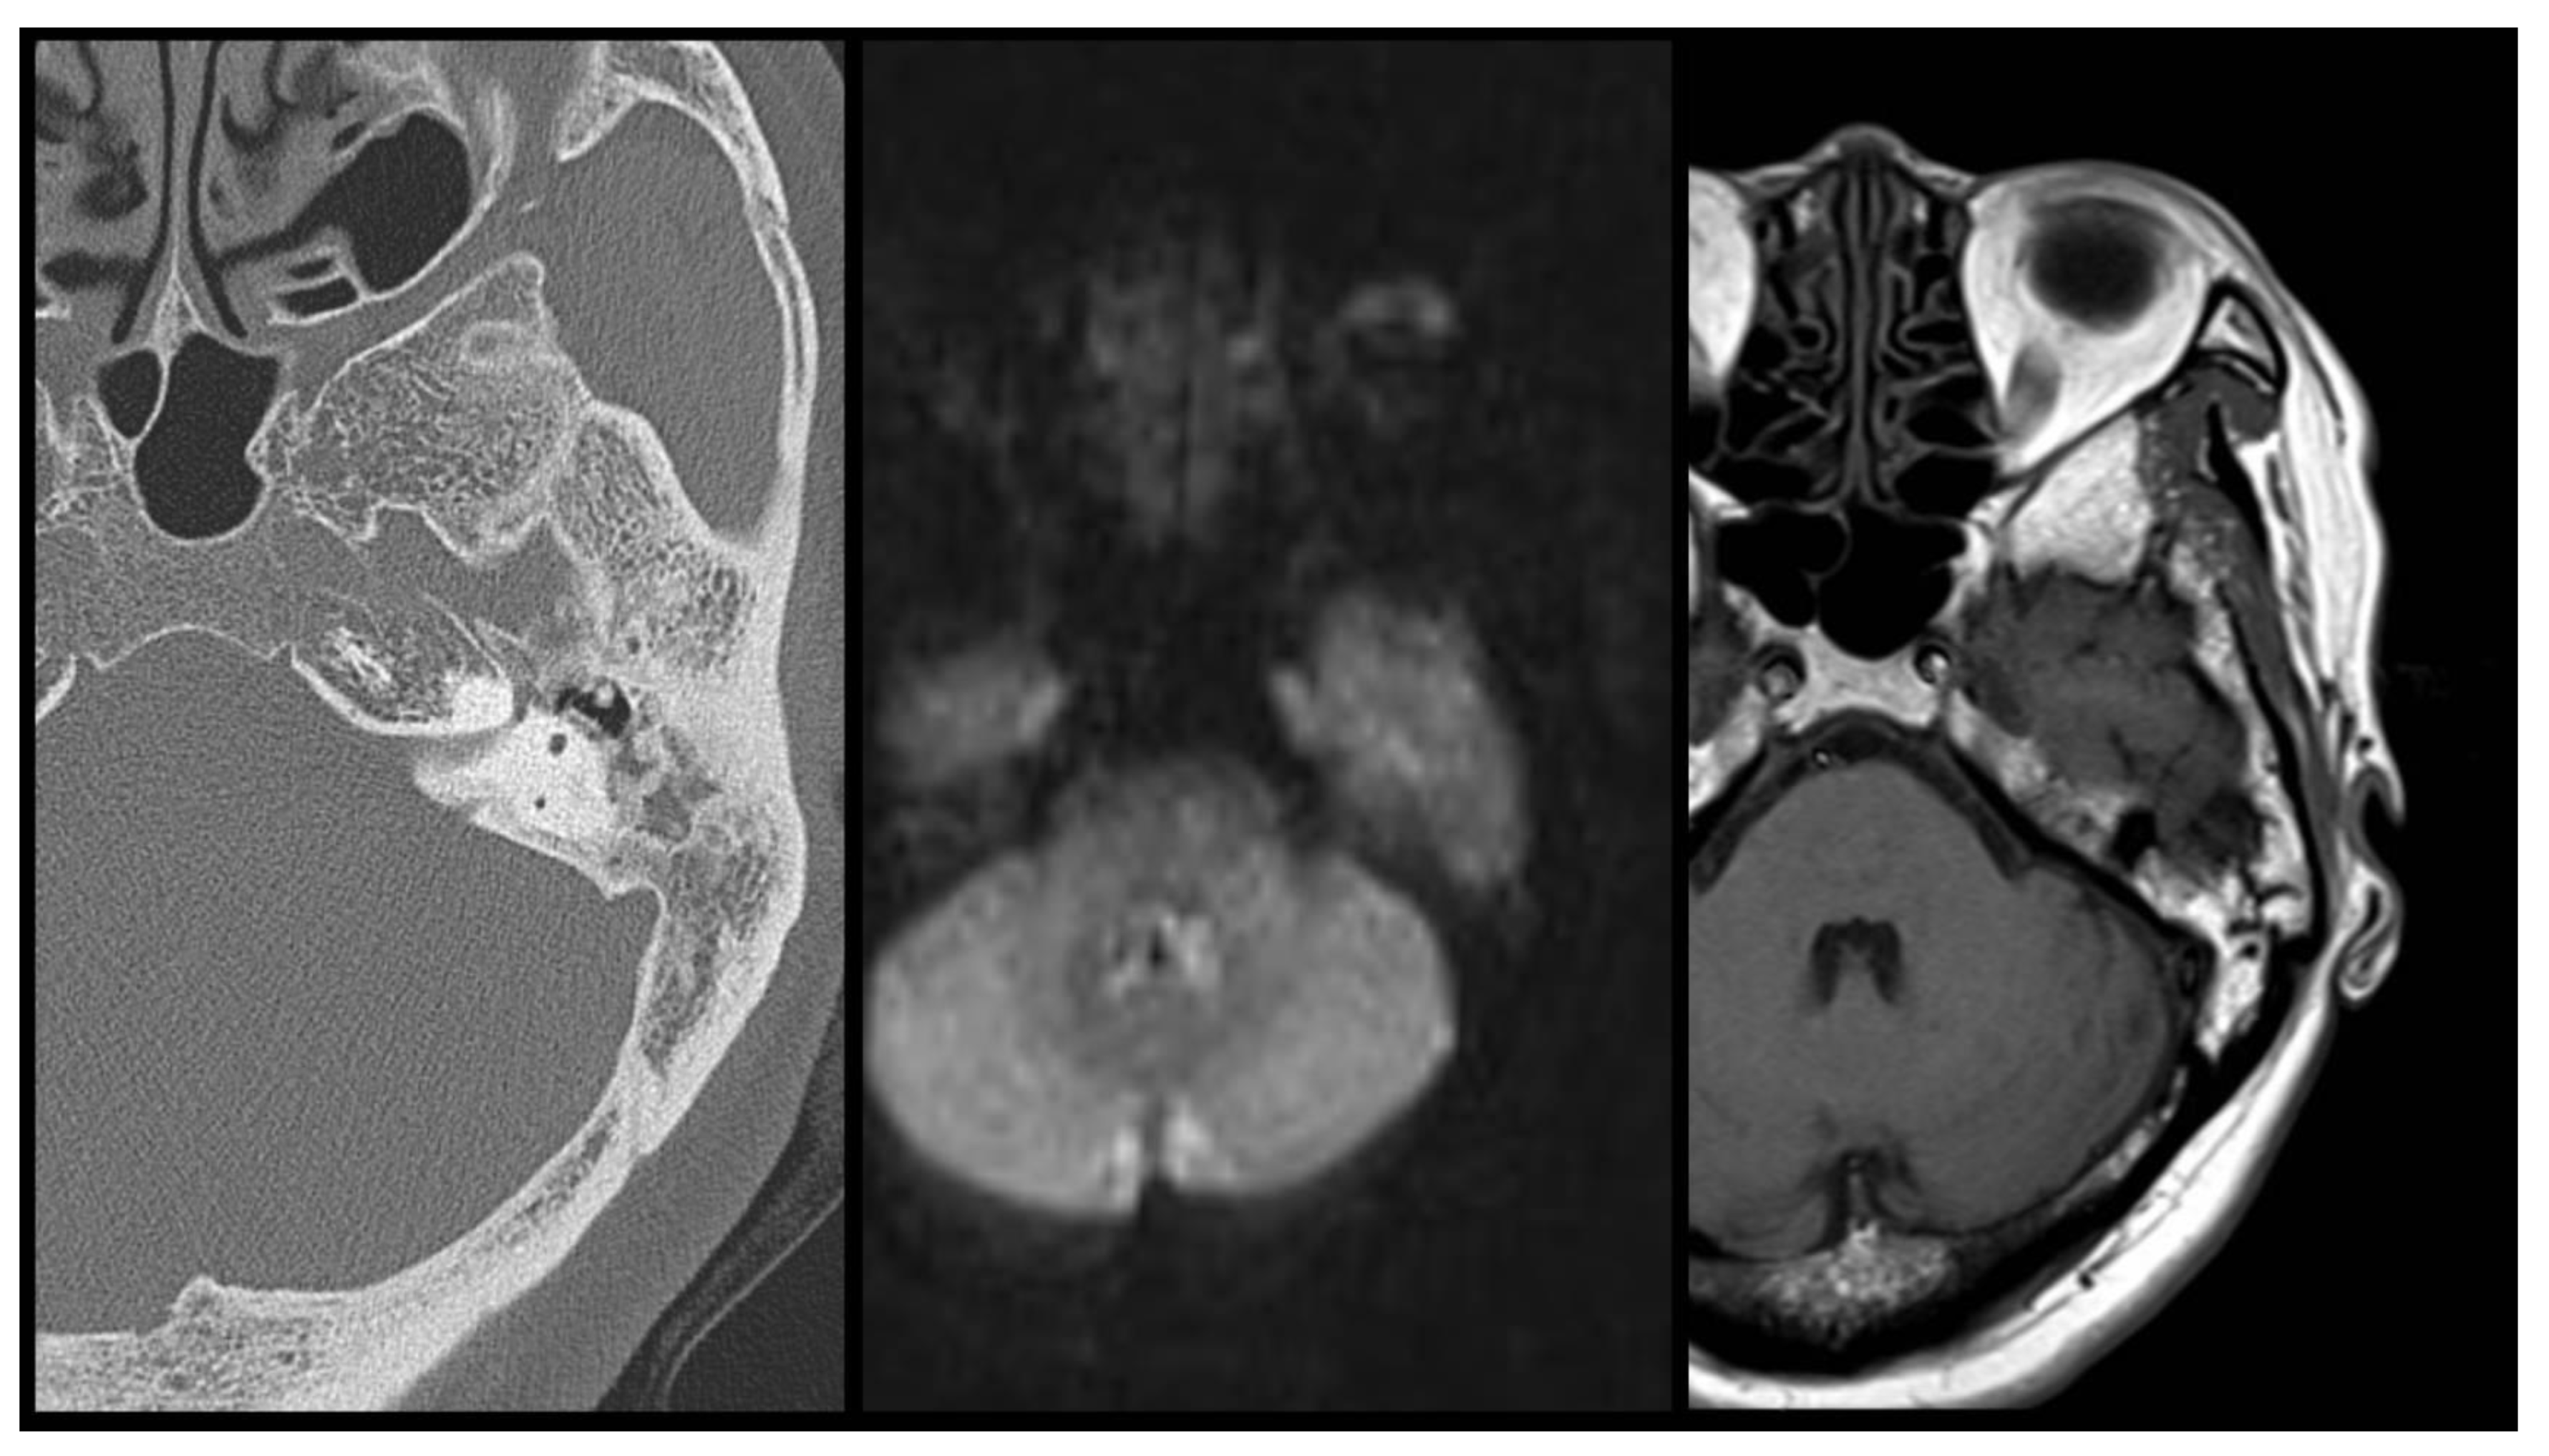

In predicting the presence of cholesteatoma, our study reveals a sensitivity of 92% (23/25 cases with cholesteatoma), specificity of 90% (9/10 cases without cholesteatoma), false positive of 4% (1/24 cases diagnosed with cholesteatoma but revealed negative with surgical finding), false negative of 18% (2/11 cases diagnosed without cholesteatoma but revealed positive with surgical finding) and an overall accurate predictive value of 91.4% (32/35 correct prediction), by way of preoperative combined DW-T1W-CT examination (Table 2). The false positive case (case 26) was originally diagnosed as otitis media with cholesteatoma, during the operation by the DW-T1W-CT images survey. However, the surgical finding revealed no cholesteatoma formation in the mastoid or middle ear cavity. (Figure 1) The false negative cases (case 24 and 25) were diagnosed as otitis media without cholesteatoma by the DW-T1W-CT images survey. Yet, during the operation, the surgical finding revealed cholesteatoma formation in the middle ear cavity or mastoid cavity (Figure 2 and Figure 3).

In this image series, CT showed mass lesion in middle ear, DWI MRI revealed hyper intensity signal and T1 MRI expressed mild peripheral ring enhancement around middle ear lesion. According to these features, otitis media with cholesteatoma is suspected in the pre-operative image evaluation. However, in the real situation, no cholesteatoma was found during the surgery or proved by the post-operative pathological diagnosis.

Figure 1. DW-T1W-CT images of false positive case (case 26). From left to right, CT-DWI-T1.